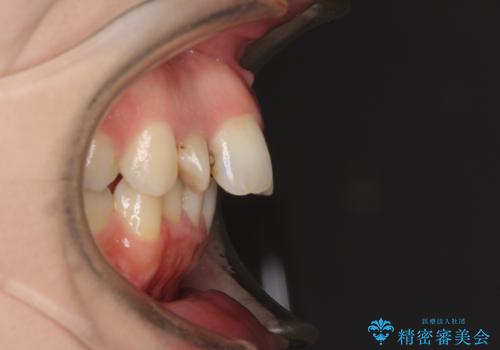

飛び出した上顎前歯とむし歯の多い歯列 目立たないハーフリンガル矯正とむし歯治療

- 上顎前歯が叢生により前方に出ている状態や、全体的なむし歯を気にして来院された患者様です。

口元の突出感を改善するために小臼歯4本を抜歯することとしましたが、左下は大臼歯が欠損していたため、そのスペースを活用し、小臼歯を3本抜歯して治療を行うこととしました。